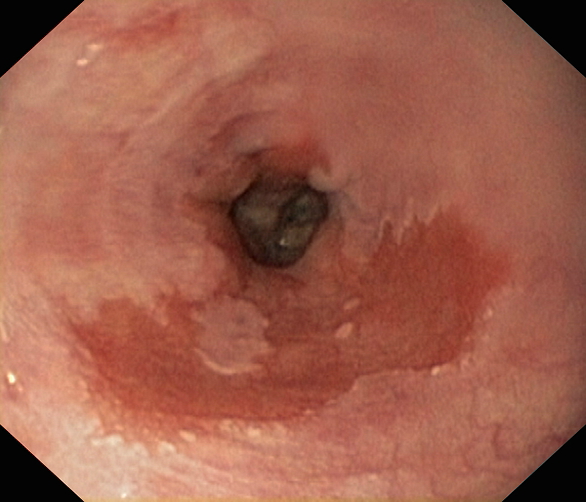

Jednym z powikłań choroby refluksowej przełyku (GERD) jest przełyk Barretta. Ten stan z kolei predysponuje do rozwoju gruczolakoraka przełyku. Istotne znaczenie w tej sekwencji zdarzeń odgrywa narażenie na kwaśną treść zarzucaną z żołądka do dystalnej części przełyku.

Jednym z powikłań choroby refluksowej przełyku (GERD) jest przełyk Barretta. Ten stan z kolei predysponuje do rozwoju gruczolakoraka przełyku. Istotne znaczenie w tej sekwencji zdarzeń odgrywa narażenie na kwaśną treść zarzucaną z żołądka do dystalnej części przełyku.

Jednym z powikłań choroby refluksowej przełyku (GERD) jest przełyk Barretta. Ten stan z kolei predysponuje do rozwoju gruczolakoraka przełyku. Istotne znaczenie w tej sekwencji zdarzeń odgrywa narażenie na kwaśną treść zarzucaną z żołądka do dystalnej części przełyku.